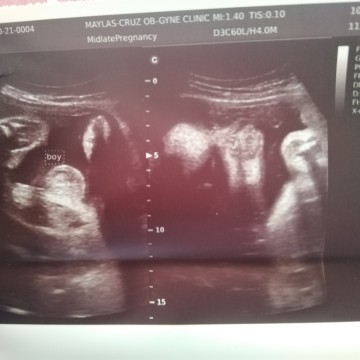

its a baby boy

hindi pala totoo ang kasabihan na kapag blooming ka , kapag di ka maselan magbuntis , kapag hindi nangitim ang kili kili at batok , at kapag hindi namaga ang ilong at kapag bilugan ang tiyan ay baby girl daw , lahat kasi ang sabi sakin baby girl daw ,pero mali pala sila